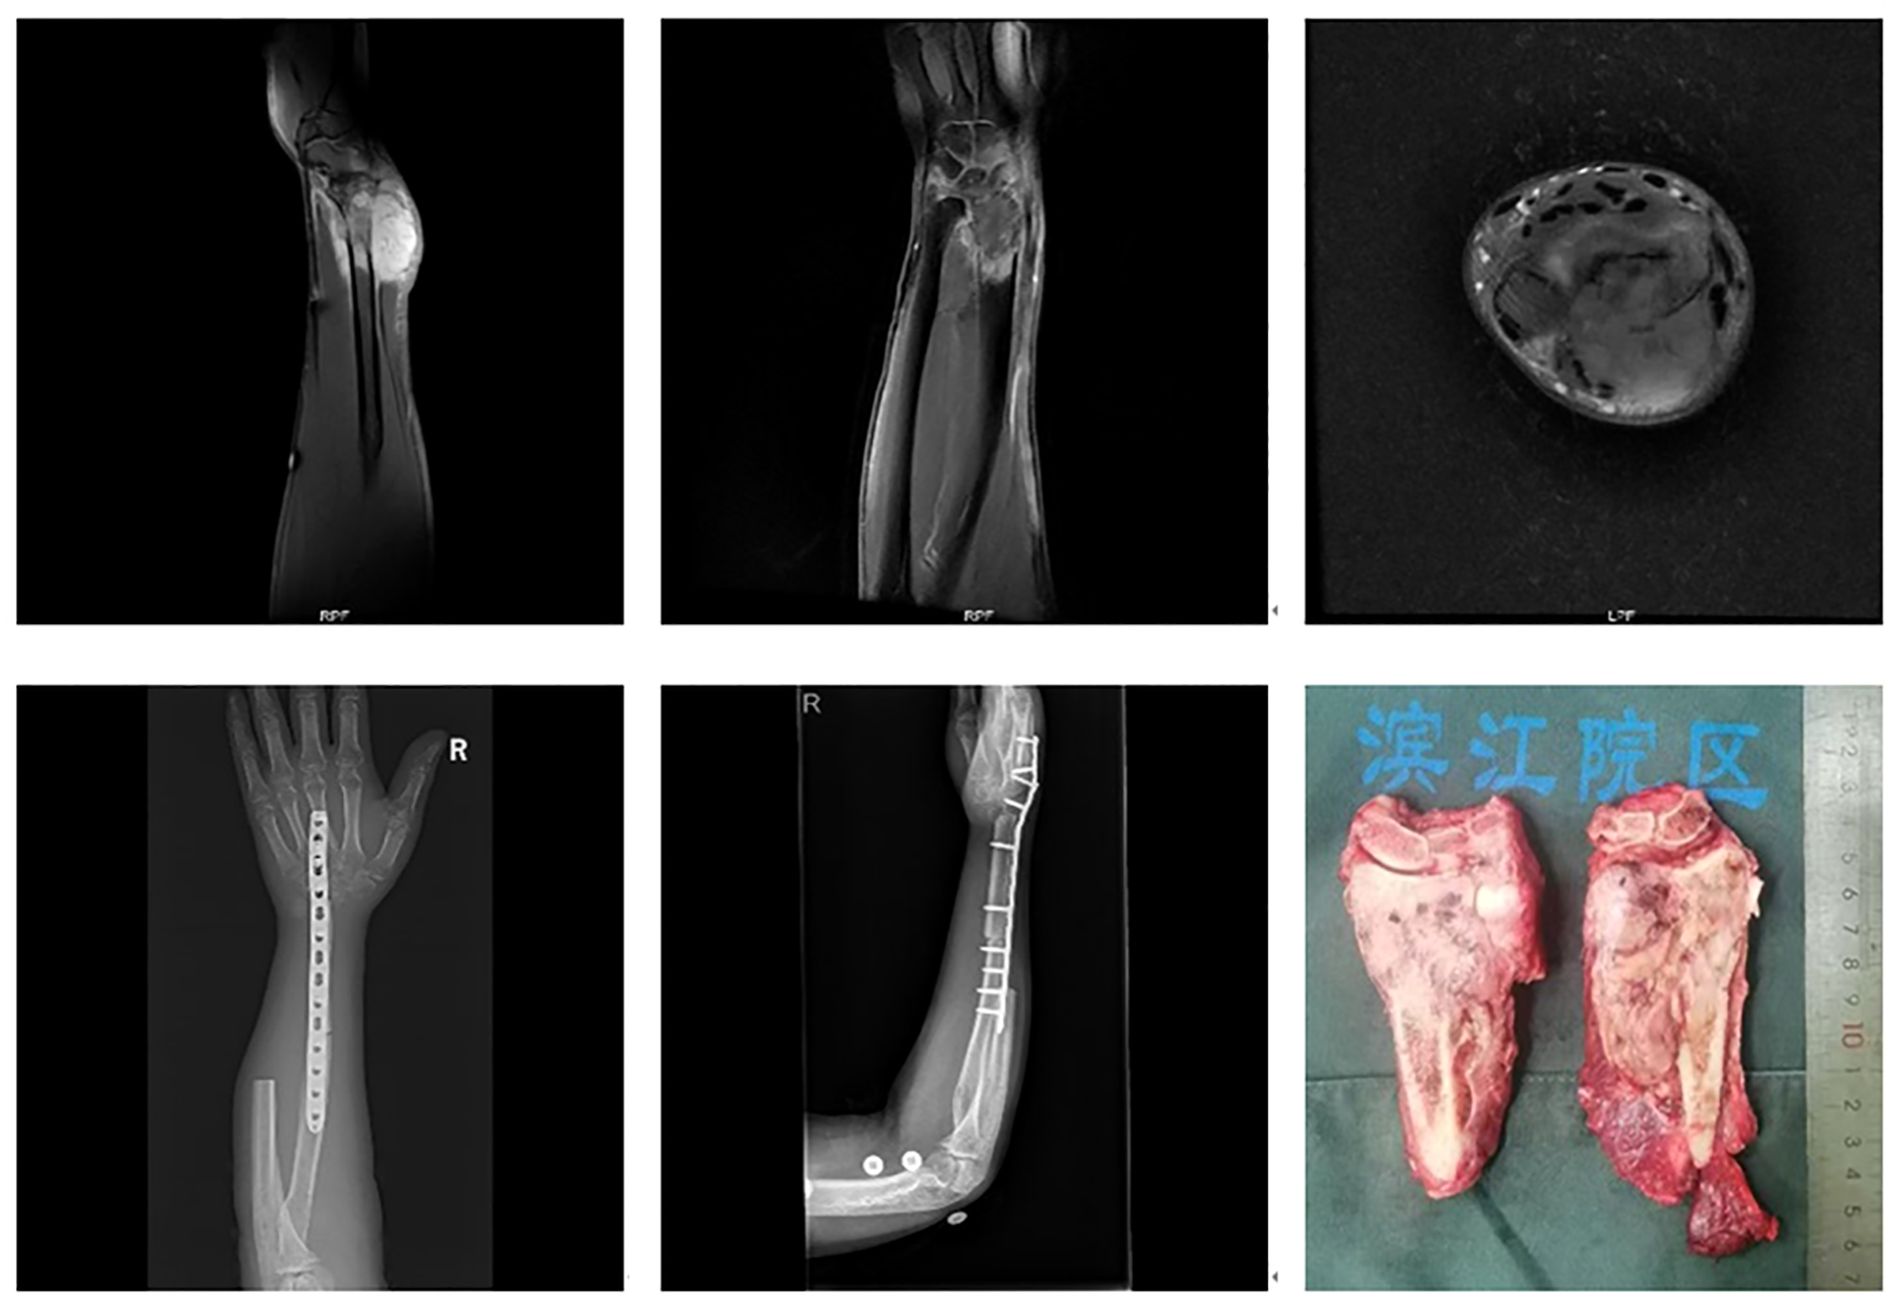

Tumors involving more than half of the distal radius (Figure 3): Reconstruction strategies included ulnar-only fixation and wrist arthrodesis.

Five cases involved extended resections: one case of distal radius and distal ulna resection, one case of distal radius and proximal carpal bone resection, and three cases involving resection of the distal radius, distal ulna, and proximal carpal bones. All cases were reconstructed with wrist arthrodesis—three using autologous fibular grafts and two using ipsilateral ulnar transposition with arthrodesis (Figure 7).

Figure 7. A 46-year-old male with leiomyosarcoma of the right distal radius, with tumor involvement extending to the distal radius, proximal carpal bones, and the distal ulnar-radial joint. The patient underwent resection of the distal radius, distal ulna, and proximal carpal bones, followed by ipsilateral ulnar transposition with arthrodesis.

Wrist arthrodesis techniques for distal radius reconstruction include the use of autologous iliac bone grafts, autologous fibular head grafts, ipsilateral ulnar transposition, and prosthetic arthrodesis. Arthrodesis is generally preferred in cases of joint instability, particularly when resection involves the proximal carpal bones and/or the distal ulna (18, 19). While autologous fibular head grafting is effective, it necessitates fibular harvesting, thereby increasing surgical complexity. In contrast, ipsilateral ulnar transposition eliminates the need for fibular grafting and has been associated with favorable outcomes and reduced complication rates. This method, first described by Seradge in 1982, has since been widely adopted for distal radius reconstruction (20–22).

In this study, one patient underwent resection of the distal radius and proximal carpal bones, another required distal radius and distal ulna resection, and three underwent resection of the distal radius, distal ulna, and proximal carpal bones. Autologous fibular head arthrodesis was employed in earlier cases; however, ipsilateral ulnar transposition with arthrodesis was favored in more recent cases due to its lower complication rate. Prosthetic arthrodesis was used less frequently, given its associated risks, while autologous fibular head grafts remained a viable option for high-grade tumors but required careful patient selection.